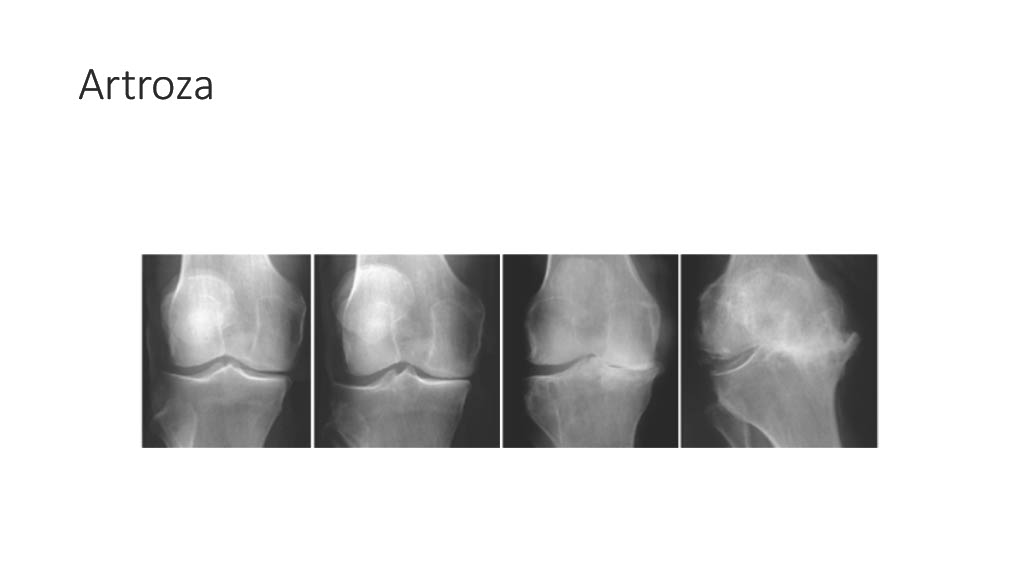

Vogrin, Matjaž, MD, PhD.

Department of Orthopaedics & Sports Medicine Institute, University Medical Centre Maribor, Slovenia

“Surgical treatment of knee injuries in skiing”

Prof. Matjaž Vogrin is an orthopaedic surgeon and specialist in arthroscopic surgery and sports injuries. He is chairman of the Institute of Sports Medicine ” at the Faculty of Medicine in Maribor, Slovenia, and head of the medical subdivision of the Slovenian National Olympic Committee.

He was chief physician of the Slovenian Olympic team at the 2012, 2016, 2021 and 2024 Olympic Games (London, Rio, Tokyo, Paris), official physician of the Slovenian national football team and head of the Slovenian medical team at the 2010 FIFA World Cup in South Africa. He has also been head of the medical team of FC Maribor ( UEFA Champions League and Europa League participants) since 1999. He has been an invited speaker at sports medicine congresses and conferences worldwide.

Surgical treatment of knee injuries in skiing